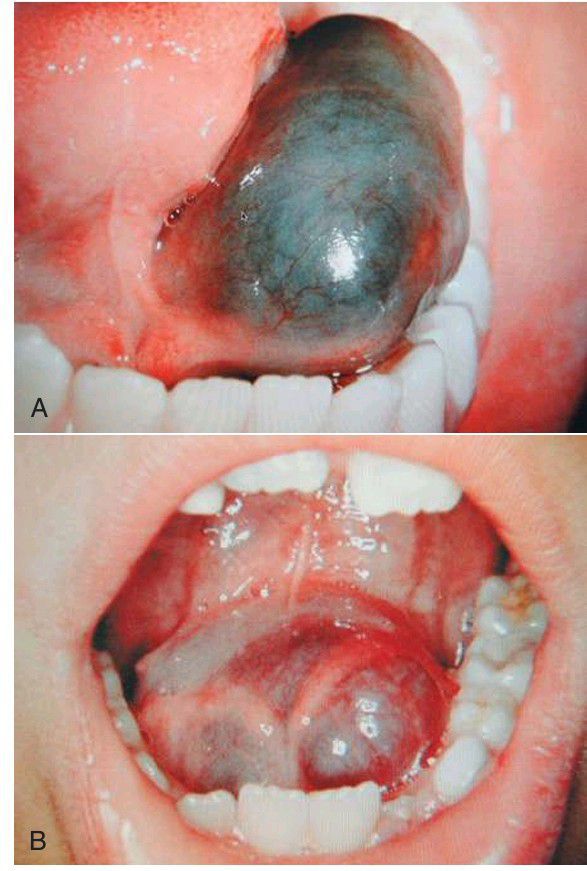

Ranula

(A) Left floor of mouth ranula. (B) Bilateral floor of mouth ranula. Note the bluish appearance of these ranulas from the high mucous (mucin) content.